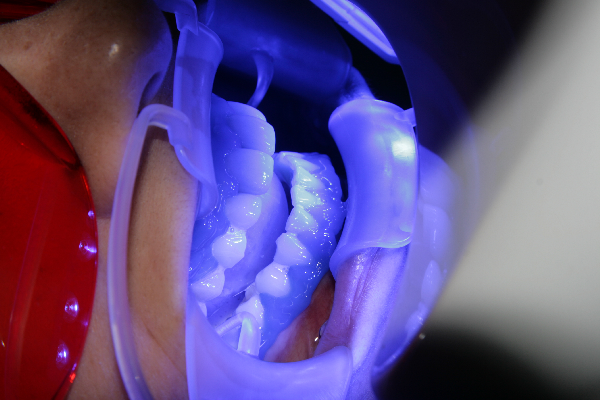

Случай на професионално избелване на пациентка на 32 г. Със системите за професионално избелване се получават добри и дълготрайни резултати, които трудно могат да бъдат постигнати при системите за домашно избелване. Все пак най-доброто избелване на зъби се получава при комбинация от двата метода - клинично и домашно избелване, като последното се прилага след избелване в кабинета като поддържащо лечение.